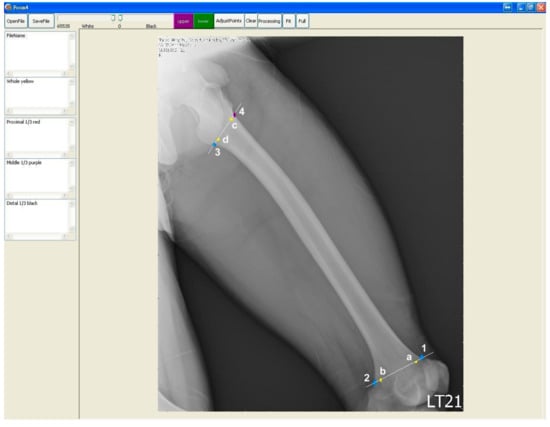

We retrieved plain radiographs of the lateral view of femur taken at Taipei Hospital, Ministry of Health and Welfare, Taiwan from January to August 2014. Initially, we retrieved 93 cases from the Image bank. The radiographs of participants with the age of more than 75 (n = 9) or less than 18 (n = 1) years old were excluded because of the special regulations of local institutional review board (IRB). Nine cases with fractures of the femur with notable displacement were excluded, too. On examining the images, the whole length of the femur had to be included in the image, the outer border of the femur and the border of the medullary canal had to also be easily outlined. Otherwise these images were excluded as well (Figure 1). Finally, 35 radiographs met the inclusion criteria (Figure 2).

Figure 1. (a) Two examples of the excluded images: Note the whole length of femur was not included in the image; (b) Fracture of the femur with notable displacement is noted in the image.